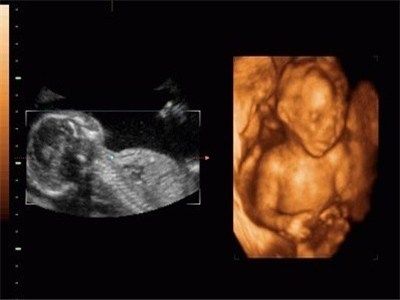

西安安琪兒婦產(chǎn)醫(yī)院引進(jìn)美國(guó)GE四維動(dòng)態(tài)彩超系統(tǒng)(4D),能夠清晰顯示出未出生寶寶的即時(shí)動(dòng)態(tài)活動(dòng)圖像,可以將寶寶的樣子和動(dòng)作制作成照片或影響光盤(pán),讓他擁有完整的零歲相冊(cè),給父母及今后的孩子留下珍貴的紀(jì)念。

2.專業(yè)超聲設(shè)備(美國(guó)GE-E8):出色的人體工程學(xué)設(shè)計(jì),它不存在射線、光波和電磁波等方面的輻射,對(duì)寶寶和孕婦健康不會(huì)造成影響。高分辨率容積成像(HD Live)、容積SRI(V SRI),新一代的4D渲染模式,圖像質(zhì)量卓越,進(jìn)一步提高臨床診斷準(zhǔn)確率。

3.4D超聲圖像質(zhì)量:4D超聲能自動(dòng)為胎兒進(jìn)行宮內(nèi)拍"寫(xiě)真"和動(dòng)態(tài)錄像,可多方位、多角度地觀察宮內(nèi)胎兒的生長(zhǎng)發(fā)育情況,為早期診斷胎兒先天性體表畸形提供科學(xué)依據(jù),超高清四維圖像質(zhì)量可以實(shí)時(shí)清晰地觀察寶寶動(dòng)態(tài)運(yùn)動(dòng)。